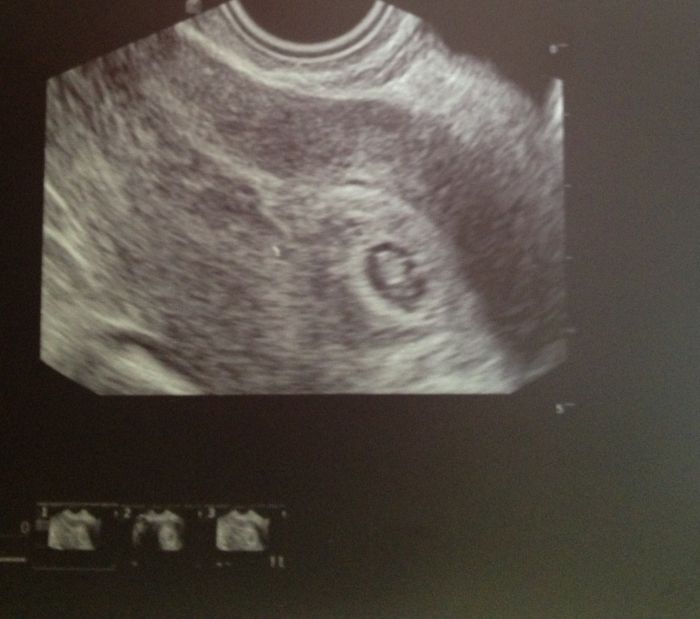

Tak jsem byla u pana doktora, velmi klidnym hlasem mi vysvetlil, ze zanik tehotenstvi je bohuzel bezna vec, ale ze se podivame na ultrazvuku. Vysetril mne, zjistil, ze nikde nic neboli, spineni tam opravdu je, ale ze je nejaky stary hematom. A prisel na radu ultrazvuk, pan doktor povida, ze to nevidi moc dobre, ze tehotentsvi opravdu vzniklo, ale asi zanika, pokud uz nezaniklo a ze mam stesti, ze se cistim sama, ze nebudu muset na sal. No krve by se ve mne nedorezal. Pak najednou povida, podivejte se a otocil na mne monitor a tam tlouklo srdicko jak ZVON. Plod skoro nebyl videt, ale srdicko otrasalo delohou. Ten kamen co ze mi spadl ze srdce muselo byt slyset az v Keni. :o)))))))) takze Kenatko je pekny ulicnik, hraje si s doktory na schovku. Jeden, ze mimodelozni, druhy, ze gravidita zadna a treti, ze jsem o nej prisla. NEPRISLA!!! Jen mne zlobi.

A mam i fotecku, 6+4 holky ja jsem tak rada. Mam neschopenku a dalsi kontrola 28.5.